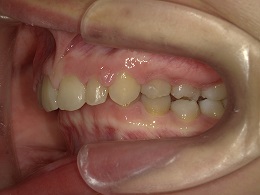

治療前右側

治療中左側

治療後右側

お試し矯正後、深い噛み合わせ改善のため上下全体矯正中の患者様の症例になります。